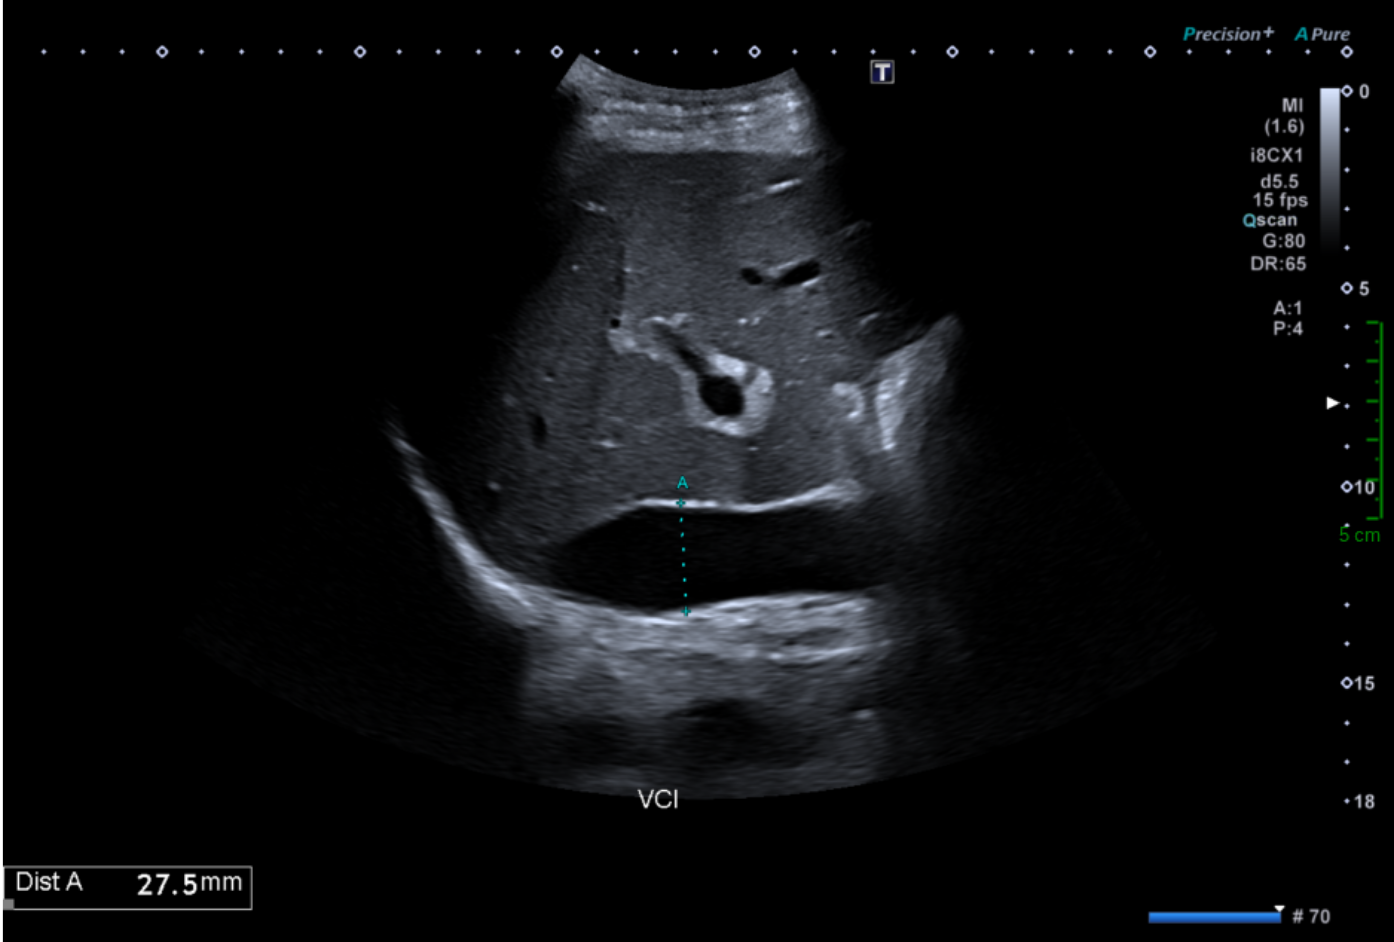

Une dilatation de la veine cave inférieure.

Le calibre normal de la veine cave inférieure varie au cours du cycle respiratoire : il est maximum en inspiration bloquée (manœuvre de Valsalva) et minimum, voire collabé, en fin d'expiration. Cette cinétique est un critère important de normalité hémodynamique. Le diamètre en expiration profonde ne doit pas dépasser 25 mm